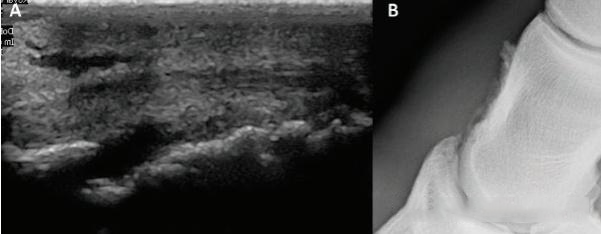

Normal Appearance: In a longitudinal view, the DDFT should appear as a highly organized, high-echoic band of parallel fibers. In a transverse view, tendons and ligaments should have a round cross-section and uniform internal echogenicity. Bursae and joint capsules should have clear walls and minimal fluid.

Pathological Signals: Any areas of hypoechoic darkening , fiber disruption or irregularity , an increase in cross-sectional area , or capsular distension are clear indicators of pathology.